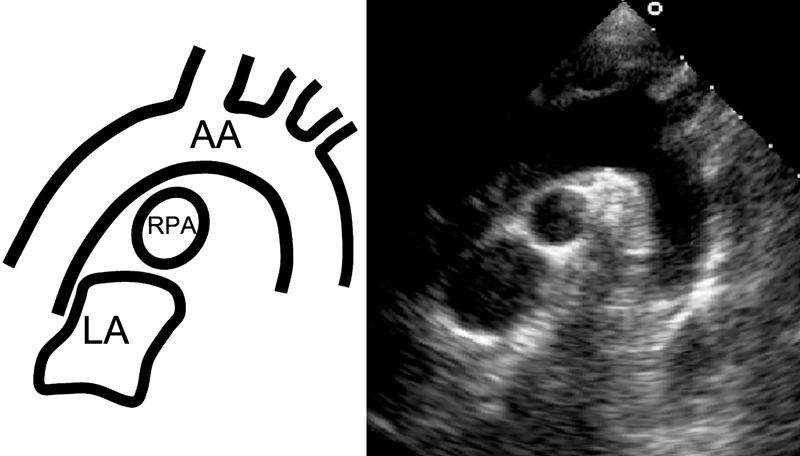

فحوصات تشخيصية لبعض امراض القلب والشرايين التاجية